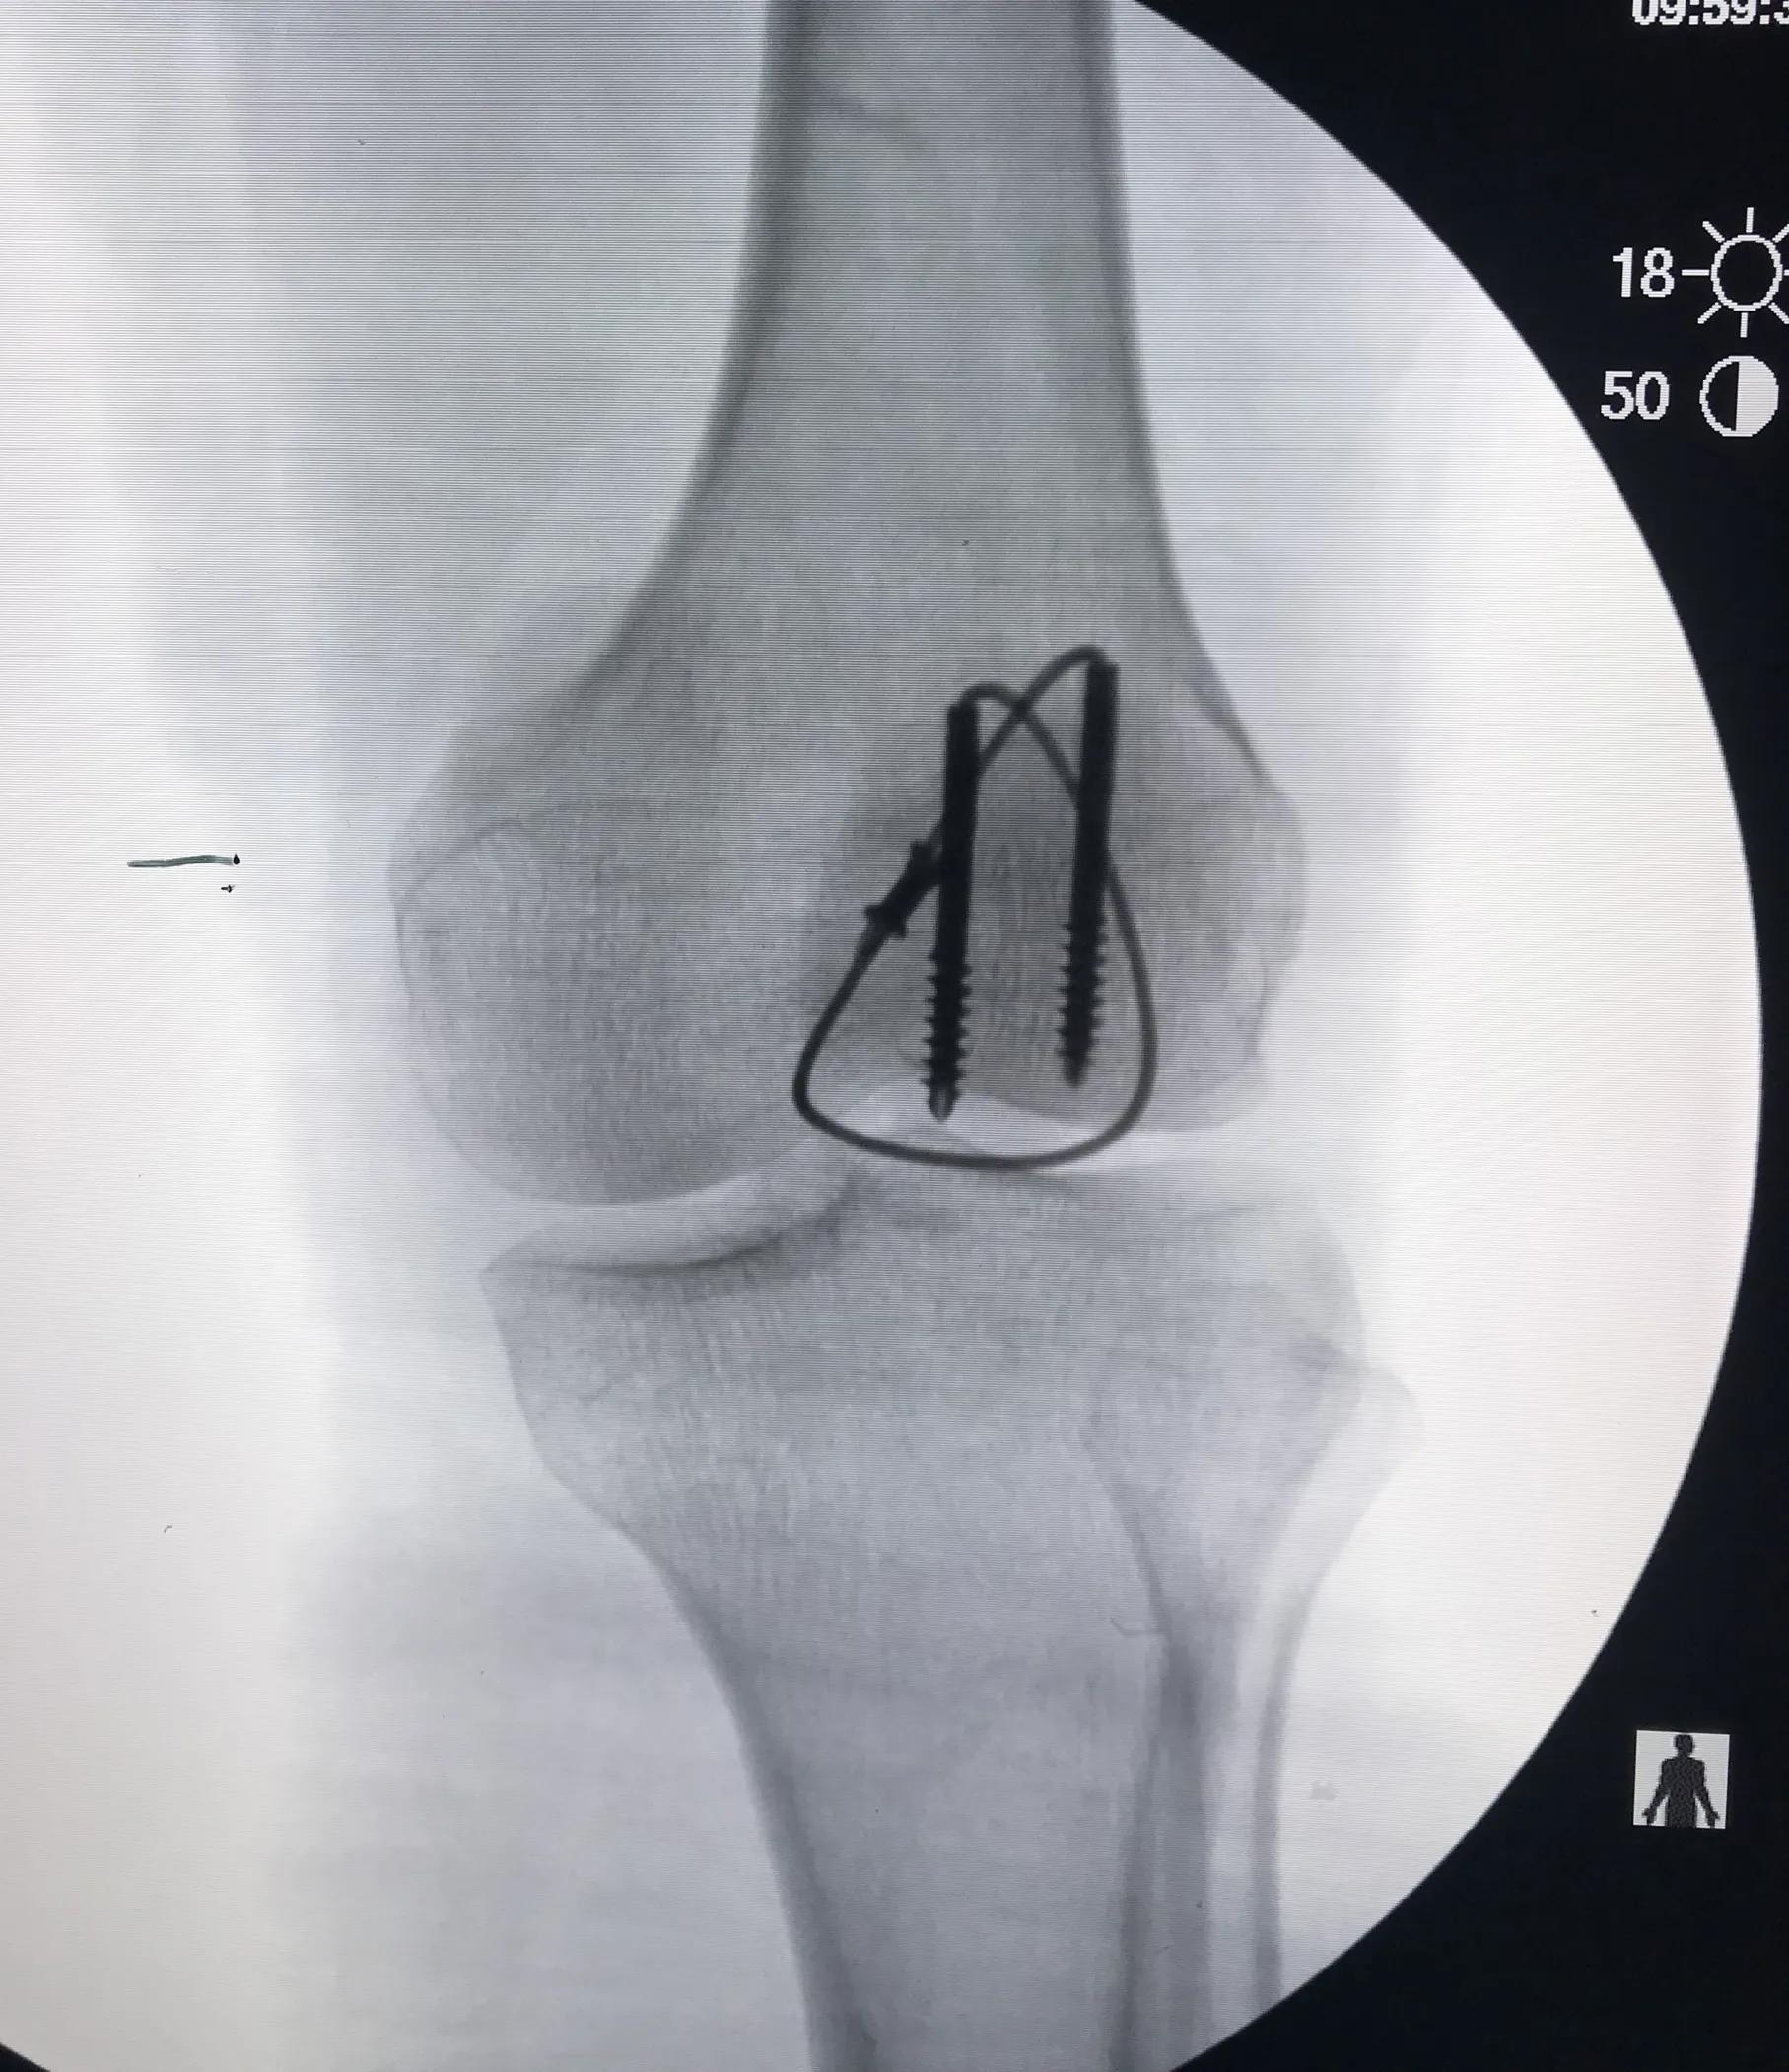

患者腰麻成功后,取平卧位,常规消毒铺巾,取膝关节纵行切口,约 10.0cm,逐层分离皮下组织及筋膜,完整暴露髌骨。复位后,应用大巾钳临时固定骨折块。C 型臂 X 光机透视下观察髌骨关节面是否平整,然后屈膝 90°,紧贴髌骨关节面由髌骨下极向上,垂直于髌骨骨折线平行打入 2 枚导针后,再次应用 C 型臂 X 光机检查导针位置。随后沿导针拧入 2 枚长度约等于髌骨纵行长度的空心拉力螺钉,拔出导针后,从空心钉内穿入钛缆,于髌前“8”字交叉,收紧钛缆并锁紧,剪除多余钛缆后,活动膝关节,检查固定的牢固性。术中需修补撕裂的髌韧带扩张部及筋膜。生理盐水冲洗手术切口后,放置引流管,逐层缝合手术切口,加压包扎。

手术中注意事项:(1)空心钉置钉位置应位于髌骨中份,最好两枚螺钉平行置钉,若螺钉偏髌骨前部,易导致关节面部分骨质失去加压作用;(2)钻入导针时最好一次成功,多次钻孔可能因钉道扩大,降低螺钉把持力;(3)空心钉应平行关节面,螺纹应完全跨越骨折线,否则不能起到初始加压作用;(4)空心钉头尾两端最好埋入髌骨内,使钛缆对髌骨起到张力带作用,避免应力传到螺钉上和钉头端切割钛缆,导致内固定失败;(5)在锁紧锁扣前,充分活动膝关节,检查骨折的稳定性和钛缆的松紧程度。